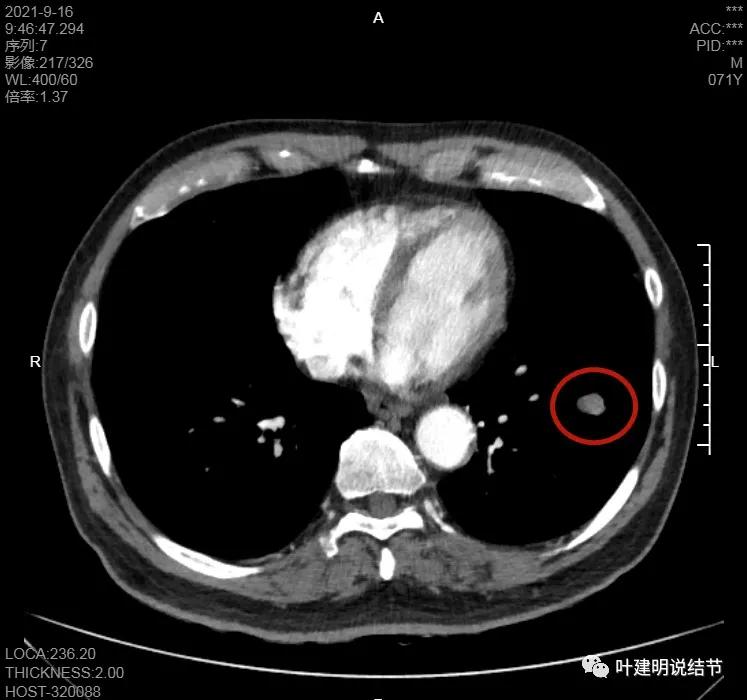

淋巴结巨大,部分包绕肺血管,但仍未见明显侵犯血管壁

肺血管受压明显,气管内壁感觉也是光滑的

以上诸图均示肿大淋巴结挤压肺血管,但未见确切侵犯破坏,支气管内壁也感觉是光滑的,没有肿瘤突向管腔